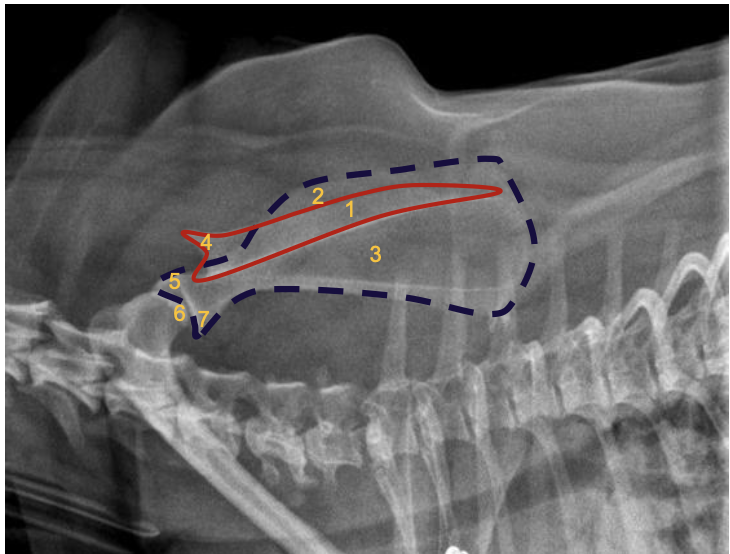

what is 1 (red box)?

spine of scapula

what is 2?

supraspinous fossa

what is 3?

infraspinous fossa

what is 4?

acromion

what is 5?

supraglenoid tubercule

what is 6?

glenoid cavity

what is 7?

infra-glenoid tuberosity